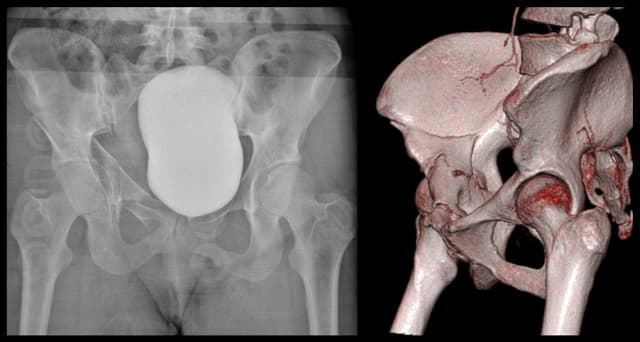

Anterior Column Acetabulum ORIF

Pre-op